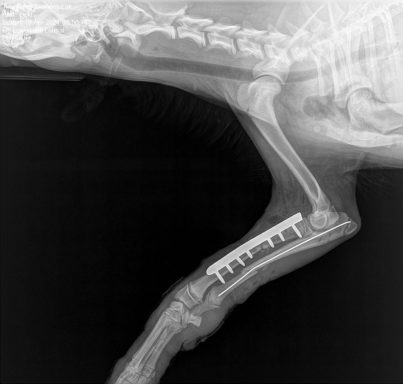

Aber auch hier in Deutschland unterstützen wir zahlreiche Hunde bei notwenigen Operationen, Tierarztkosten und vielem mehr.

# Notfall Hündin Lieselotte

Wir erwarten Lieselotte ...